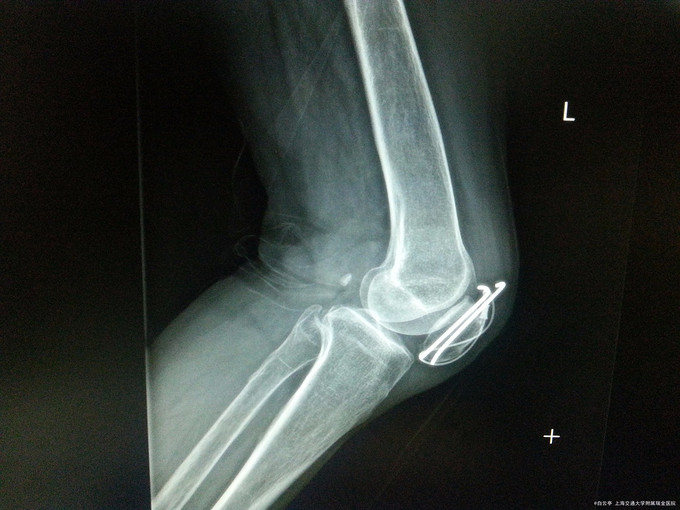

主诉:左髌骨骨折ORIF术后11个月 病史:患者,女,66y。患者11个月前因“左髌骨骨折”我院全麻下行“左髌骨骨折切开复位内固定术”。术顺,患者恢复良好予以出院。术后患者定期复查骨折愈合情况,目前患者复查左膝部平片示骨折愈合良好,患者无切口处疼痛红肿热痛、无左下肢末梢苍白、麻木等缺血表现,无畸形愈合,无肌无力等不适,现为取出内固定再次入院。

查体:左膝部可见陈旧性手术疤痕,局部无畸形,无肿胀,无压痛,皮肤无瘀斑。左膝关节活动度正常。远端肢体运动感觉皆正常。 辅检:左膝部平片:左侧髌骨骨折内固定术后改变。

诊断:左髌骨骨折术后取出内固定装置 治疗:入院评估患者骨折恢复可,行“左髌骨骨折术后取出内固定装置”